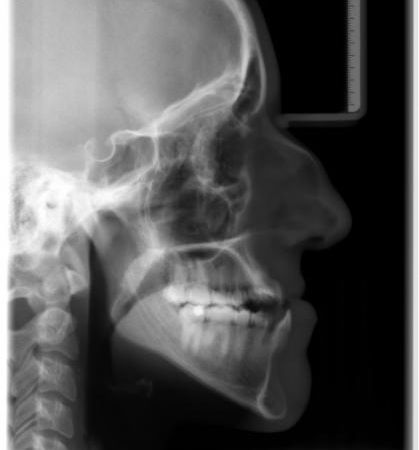

Röntgenbefund

Zu Behandlungsbeginn und nach der Operation

Die Verlagerung der Kieferbasen, v.a. im Unterkiefer, ist deutlich zu erkennen. Ferner sieht man auf dem rechten Bild die Metallplatten aus Titan, die die Knochenfragmente während der Heilungsphase in der gewünschten Position zusammenhalten. So wird frühzeitig sichergestellt, daß der Patient wieder normal kauen kann. Die Metallplatten können nach ca. 6 Monaten in einem Zweiteingriff entfernt werden.